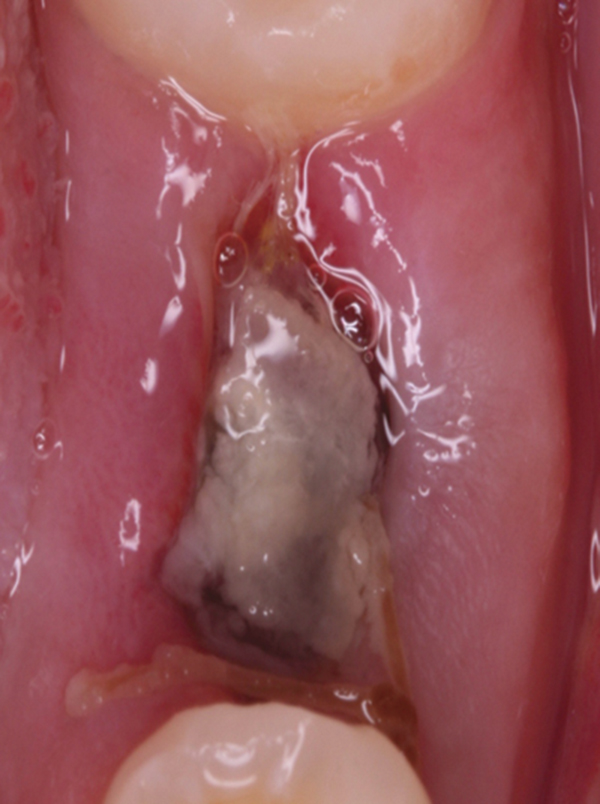

Observed Healing of an Immediately Placed Implant in a Molar Site

Product Name: Granulation tissue tooth extraction clearance